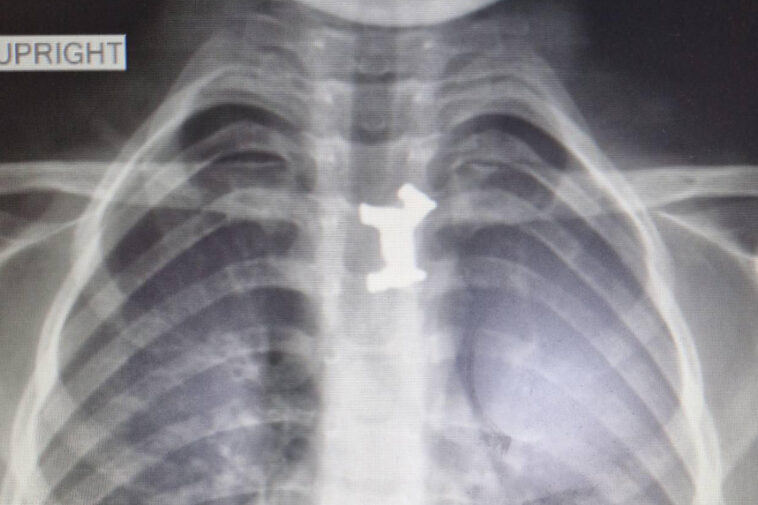

Η ακτινογραφία έδειξε το ακριβές σημείο στο οποίο είχε σφηνώσει το μεταλλικό παιχνίδι. Το πρωί το αγοράκι υποβλήθηκε σε χειρουργική επέμβαση. Οι παιδογαστρεντερολόγοι μαζί με τους παιδοαναισθησιολόγους κατάφεραν να αφαιρέσουν με επιτυχία το μεταλλικό σκυλάκι από τον οισοφάγο του ανήλικου. Ο μικρός νοσηλεύεται προληπτικά και είναι καλά στην υγεία του. Το σκυλάκι προερχόταν από γνωστό επιτραπέζιο παιχνίδι για παιδιά μεγαλύτερης ηλικίας.